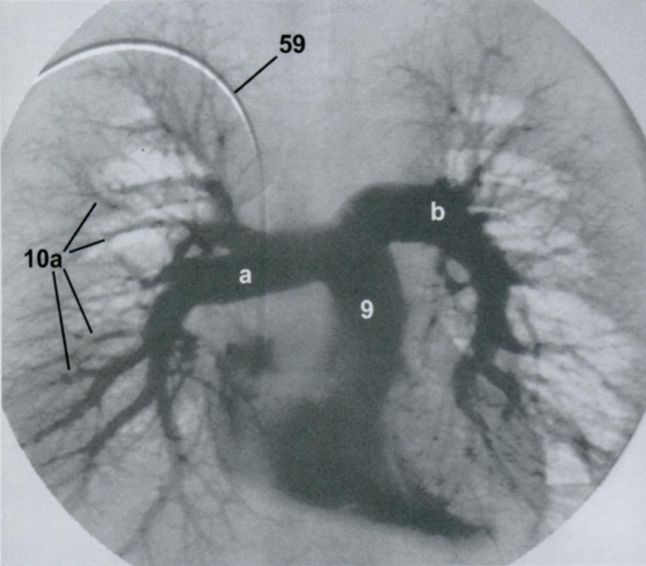

18

Q

Ангиографическая визуализация сосудов легких.

Какая фаза распространения контраста? Артериальная или венозная?

Назовите все пронумернованные структуры.

Задняя прямая проекция (ЗПП)

Ангиография выполняется с помощью введения контраста через катетер в полой вене, правом предсердии или артериях малого круга.

A

Артериальная фаза. Норма.

9 - легочный ствол

9а - правая легочная артерия

9b - левая легочная артерия

10а - легочные артерии

59 - катетер